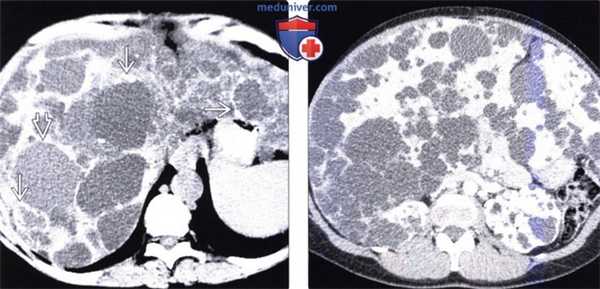

(Слева) На аксиальной КТ без контрастного усиления определяются множественные кисты однородной структуры, низкой плотности, с ровной и тонкой стенкой. Внутренняя структура кист не изменена. В некоторых кистах находится содержимое с плотностью, которая превышает плотность воды, в периферических отделах других кист (в стенке) визуализируются кальцинаты, обусловленные «старым» кровоизлиянием.

(Справа) На аксиальной КТ с контрастным усилением визуализируется увеличенная печень со множественными кистами. Обратите также внимание на кистозные изменения обеих почек. У большинства пациентов поликистоз печени сочетается с аутосомно-доминантной поликистозной болезнью почек.